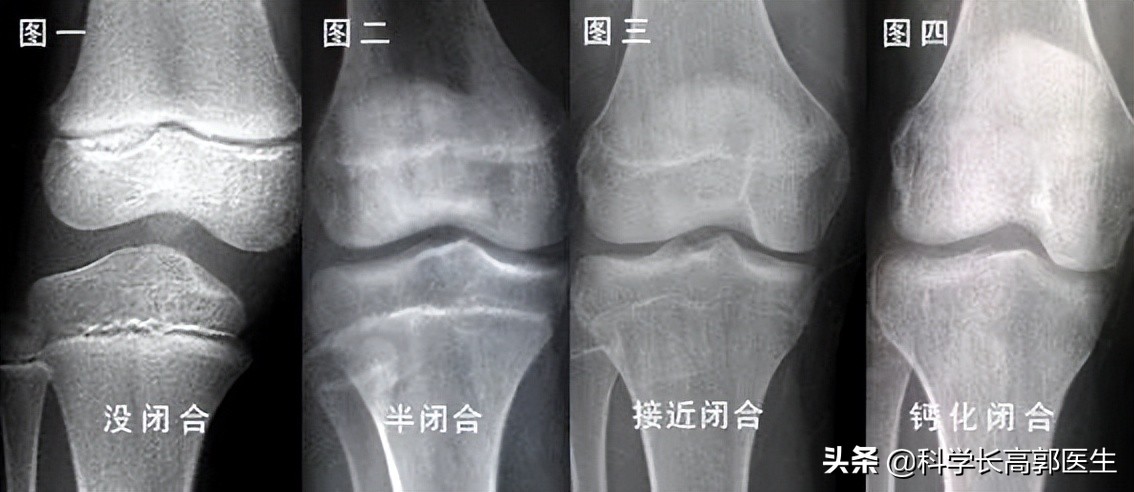

门诊遇到一个男孩,16岁了,身高只有1米45,他进门的时候,我以为是一个十一二岁的孩子,非常瘦小,胳膊上几乎没有肉,瘦到甚至可以用皮包骨头来形容。其实即便是12岁,男孩子1米45的身高也很不理想了,何况他已经16了。更令人痛心的是,看了他的骨龄片,骨骺线已经闭合了,身高算是定型了。

我之前也说过,骨骺线闭合了,是不可能再打开的,孩子基本是没有生长空间了。我之所以说基本,是因为坐高还有1到2公分的空间,也就是脊柱还能长那么一点,但家长也知道,这其实是微乎其微的。所以这个孩子现在的情况,就十分令人遗憾。